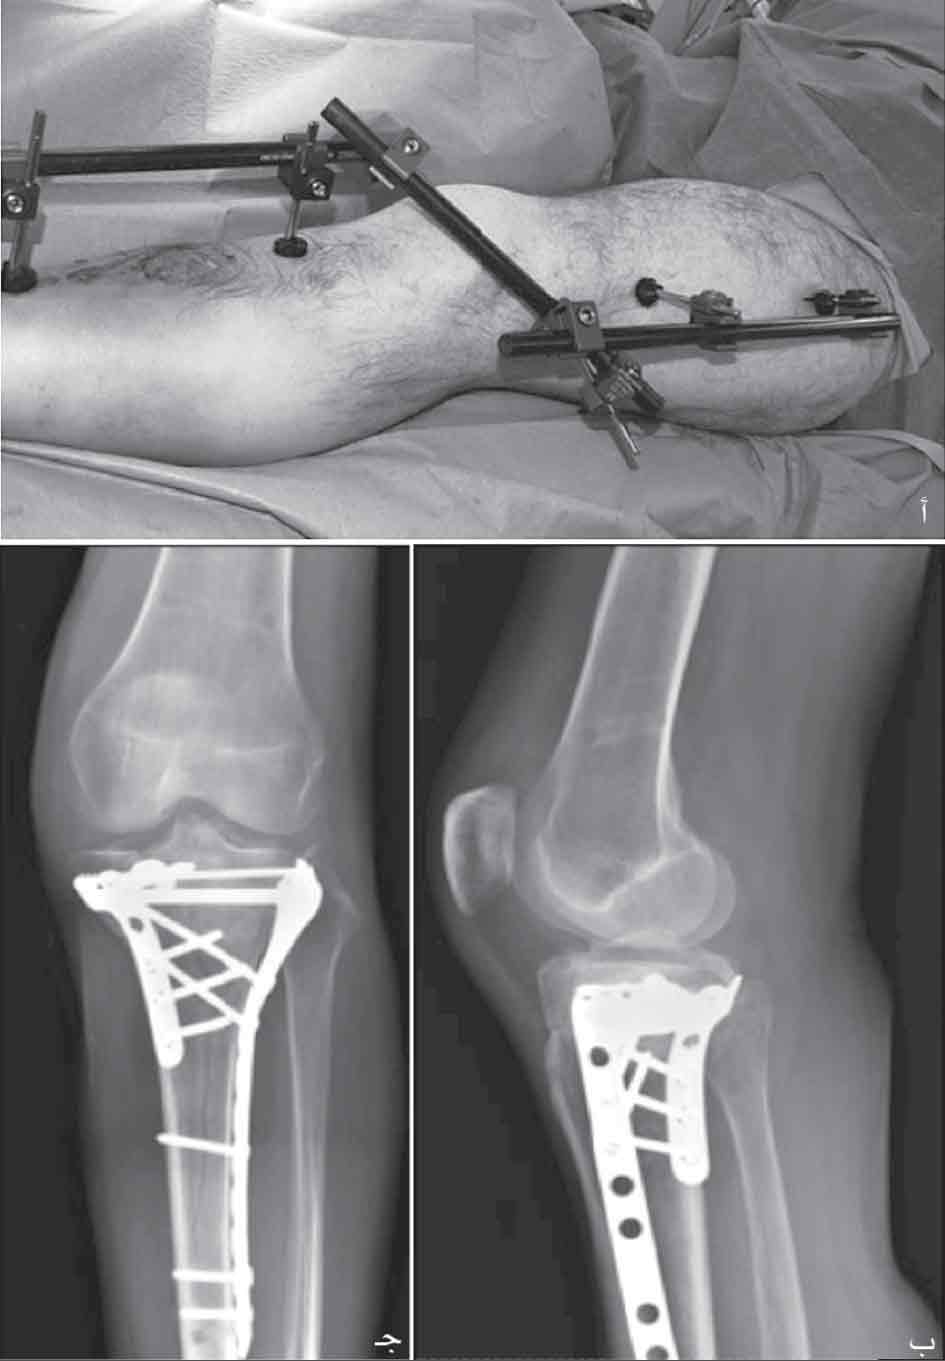

-1 وضع جهاز تثبيت خارجي عابر للركبة ويجتنب بذلك المساس بالكسر وبأنسجته الرخوة. يسمح هذا التثبيت المؤقت مدة 2-3 أسابيع بشفاء الأنسجة الرخوة من تداعيات الرض البدئي، ويُجرى بعدها التثبيت الجراحي عبر مدخلين: أمامي وخلفي إنسي مع تثبيت قطع الكسر بصفائح دعم (الشكل8).

الشكل (8) أ- جهاز تثبيت خارجي عابر للركبة لتثبيت الكسور نموذج 5 و6 ، ب-ج استجدال الكسر بصفيحتين بعد 3 أسابيع حين شفاء